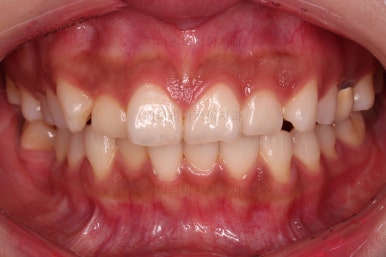

4. 마무리

할 수 있는 부분과 수용한 부분을 구분해서 환자분과 적절히 치료계획을 타협하고요. 치료를 마무리합니다.

가지런한 느낌 좋고요.

교합도 잘 맞고 이 뽑은 자리도 틈이 없으며 사랑니 당겨온 자리도 틈새 없이 잘 마무리가 되었네요.

다만 앞니가 예전에 부러져 있어서 형태저긍로 조금 부족하긴 했지만 나쁘지 않았습니다.

연산동교정치과 전후 비교해 보겠습니다.

전반적으로 깔끔하게 임플란트 없이 결손치아 부분을 잘 마무리 했습니다.